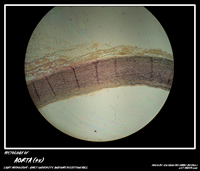

MBBS Batch 12 Histology MicroPhoto Archive

BLOOD VESSEL